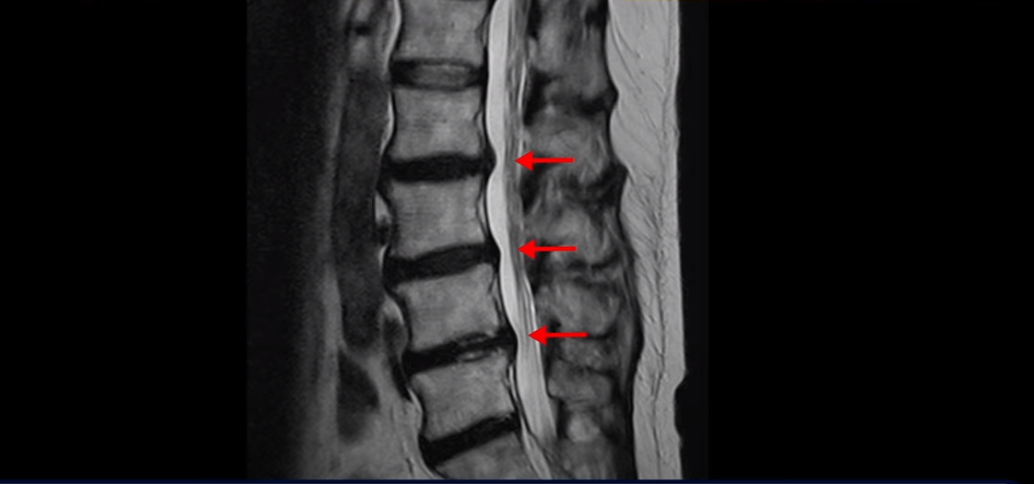

이분 MRI를 보면 여러 마디가 퇴행이 진행되어 있고

3번 4번과 4번 5번에 중심성 협착이 있는데

4번 5번이 더 심합니다.

또 4번 5번 마디에 오른쪽으로 찢어져서 밀려나온 디스크 탈출이 보입니다.

밀려나온 수핵이 조금 흘러내려 있습니다.